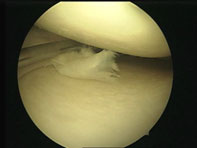

| Повреждение тела медиального мениска правого коленного сустава | Повреждение тела и заднего рога медиального мениска левого коленного сустава | Выполненная резекция заднего рога медиального мениска |

В операционной делается два небольших разреза (около 5 мм каждый), и в полость сустава вводится артроскоп. Затем в сустав закачивается специальная стерильная жидкость, полость сустава расширяется и появляется возможность увидеть состояние менисков, связок, хрящей и т. п.